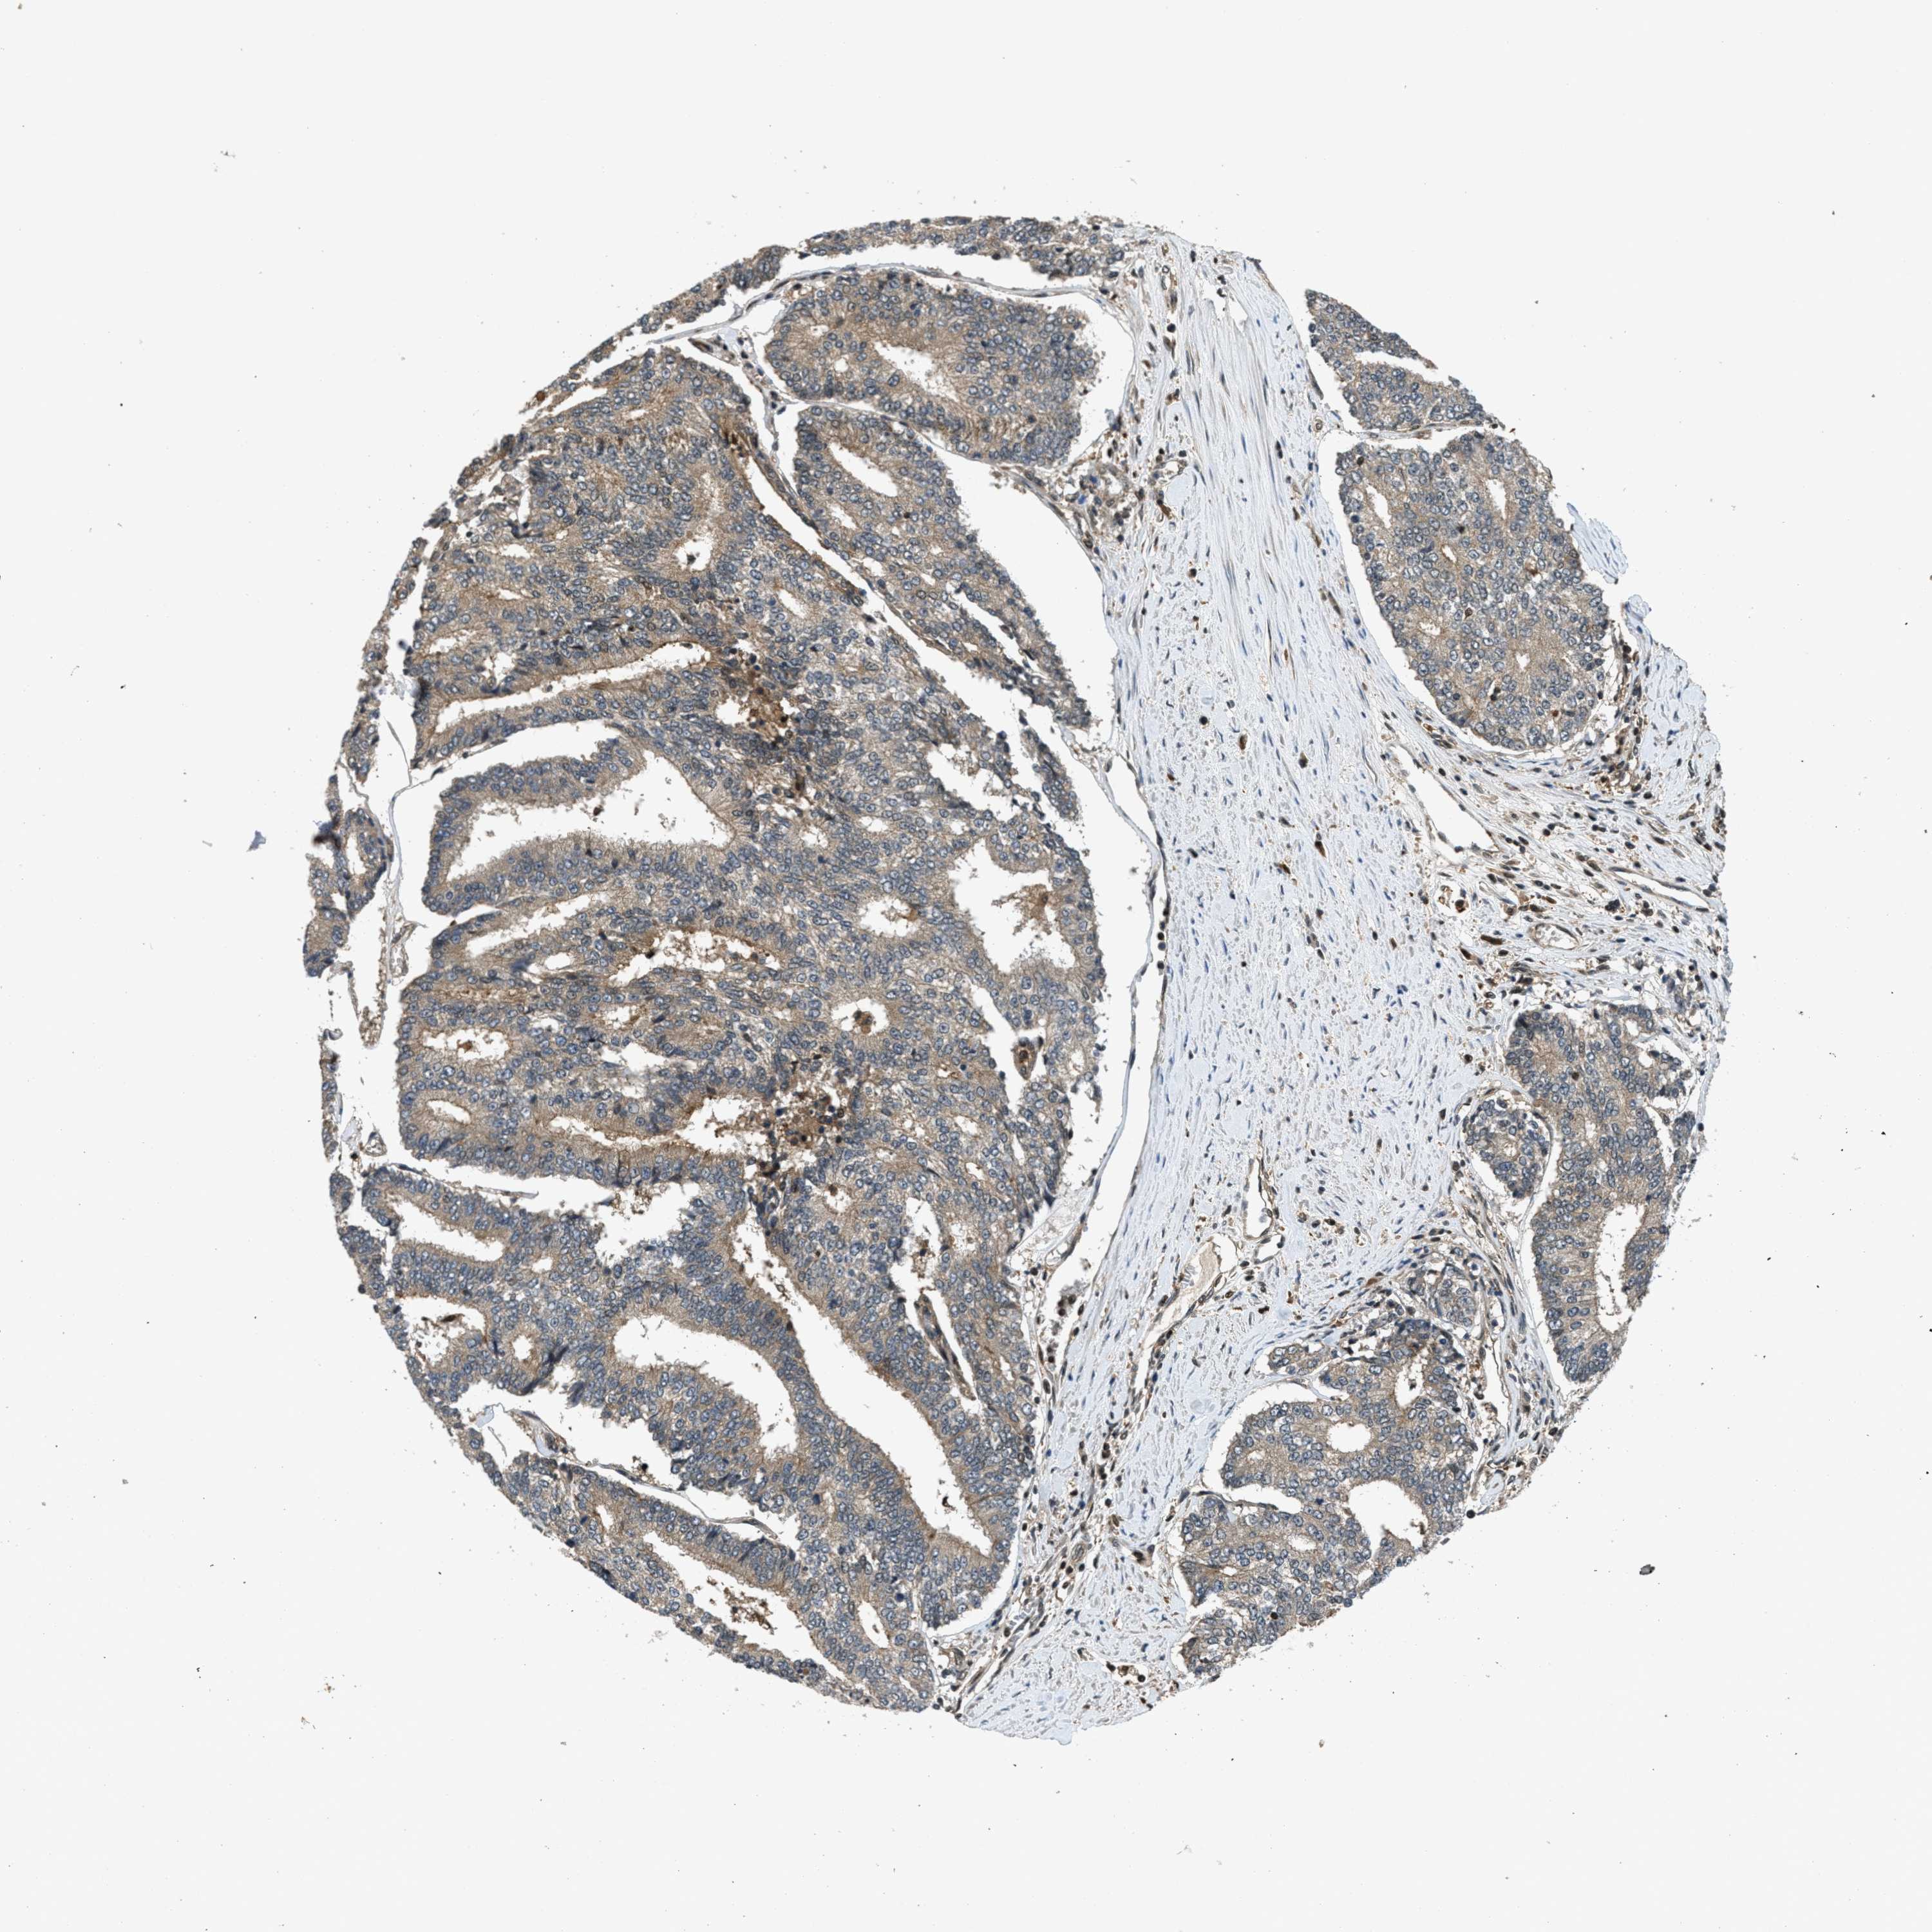

PROSTATE CANCER - Protein expressioni

A mouse-over function shows sample information and annotation data. Click on an image to view it in a full screen mode. Samples can be filtered based on level of antibody staining by selecting one or several of the following categories: high, medium, low and not detected. The assay and annotation is described here.

Note that samples used for immunohistochemistry by the Human Protein Atlas do not correspond to samples in the TCGA dataset.

Antibody stainingi

Antibody staining in the annotated cell types in the current human tissue is reported as not detected, low, medium, or high, based on conventional immunohistochemistry profiling in selected tissues. This score is based on the combination of the staining intensity and fraction of stained cells.

Each image is clickable and will lead to virtual microscopy that enables deeper exploration of all samples and also displays staining intensity scores, fraction scores and subcellular localization as well as patient and tissue information for each sample.

Antibody CAB017566

Staining

High

Medium

Low

Not detected

Intensity

Strong

Moderate

Weak

Negative

Quantity

>75%

75%-25%

<25%

None

Location

Nuclear

Cytoplasmic/membranous

Cytoplasmic/membranous,nuclear

Adenocarcinoma, High grade

Adenocarcinoma, Low grade